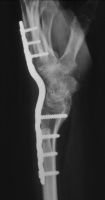

| She had progressive deterioration over two years with worsening pain and instability. |

| Eventually, she was treated with wrist fusion, distal ulnar resection and extensor carpi ulnaris tenodesis, and basal joint excision arthroplasty with split abductor pollicis longus anchovie interposition and ligament reconstruction - all through a single dorsal approach.: |